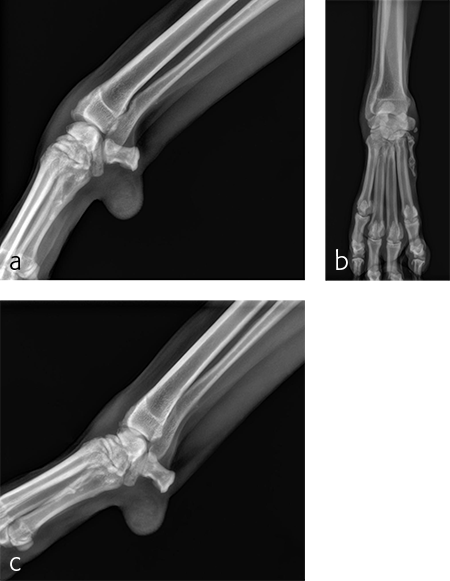

A 5-year-old neutered male Labrador Retriever weighing 24.6 kg presented with a right forelimb lameness of 4-month duration. The lameness occurred acutely and the dog was initially nonweight-bearing. The cause of the injury was not observed. Physical examination revealed a weight-bearing lameness of the right forelimb. The region of the right carpus was swollen compared to the left due to periarticular soft-tissue proliferation. A mild increase of synovial fluid and joint capsule distension was palpated. The right carpus was painful on extension and could be hyperextended to 30 degrees. The normal left carpus would extend to 10 degrees, which is the normal range of motion. Mild muscle atrophy of the right forelimb was observed. The neurological exam was normal. Radiographic examination revealed mild hyperextension, periarticular soft-tissue proliferation, and mild osteoarthritis (Fig 3). It was difficult to determine the joint level of instability of the right carpus based on the radiographic views. A diagnosis of hyperextension injury of the right carpus was made. The surgical plan included arthroscopic examination of the right carpus to assess the antebrachiocarpal joint to determine if it was affected, which would necessitate a pancarpal vs partial carpal arthrodesis.

A 7-year-old, 32.5 kg, Labrador Retriever became acutely lame on the left thoracic limb while catching a ball. It was evaluated three weeks later and had carpal swelling, pain, and instability of the left carpus. Flexed lateral, craniocaudal, and extended mediolateral view images of the left carpus revealed a dorsal chip fracture at the carpometacarpal joint and hyperextension of the left carpus (Fig 9).